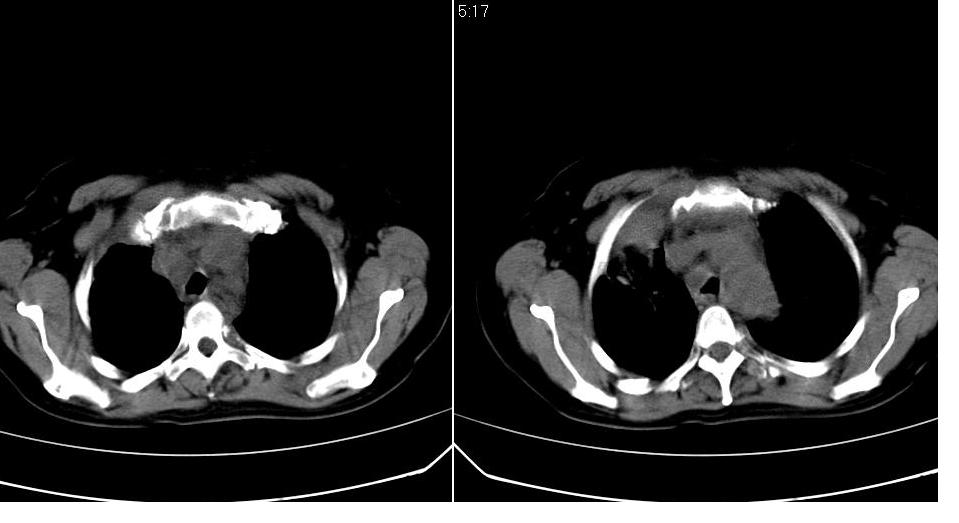

标题: CT16839:胸部CT平扫

女 50岁,在其他医院确诊肺癌.

支持 右肺上叶肺癌并两肺及纵隔转移。

肺癌并肺及纵隔转移